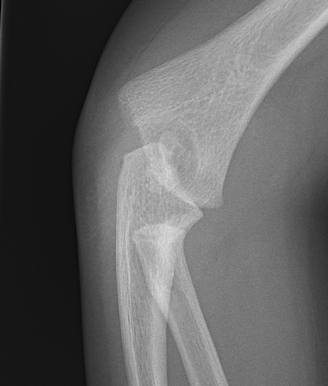

Xray

Distal physis not ossified < 1 year

- radius and ulna lose normal association with distal humerus

- posteromedial displacement of the ulnohumeral joint

- appears like an elbow dislocation

- disruption of radio-capitellar line